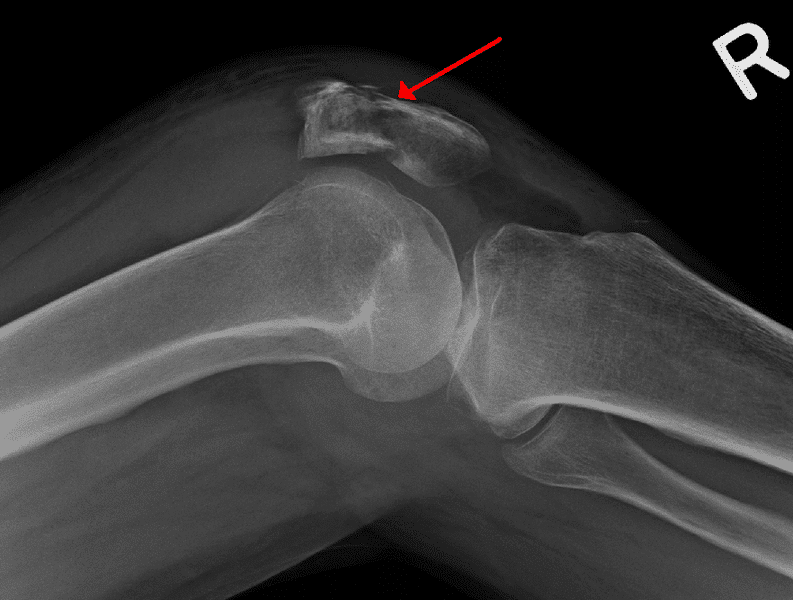

Patella fracture Image

Patellar Sleeve Fracture The Western Journal of Emergency Medicine Patella Fracture X Ray View Patellar fracture is one of the common knee injuries usually post direct trauma to the patella or sudden forceful contraction of the. A 'skyline' or 'sunrise' view is rarely indicated in the context of trauma. A skyline view can only be acquired if the patient can tolerate knee flexion. Aim 2.5cm distal to medial epicondyle. This view is only necessary. Patella Fracture X Ray View.